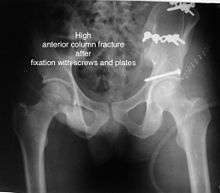

Anterior column fracture

Types: Depending on the location, the fractures are described as very low, low, intermediate and high anterior column fracture.

How to diagnose: Best seen in Obturator oblique view

CT scan helps in identifying impaction of bone pieces and if there are pieces in the joint

Treatment: if the femur head is dislocated, it should be reduced as soon as possible, to prevent damage to its blood supply. This is preferably done under anaesthesia, following which, leg is kept pulled by applying traction to prevent joint from dislocating.

The final management depends on the size of the fragment(s), stability and congruence of the joint.

In some cases traction for six to eight weeks may be the only treatment required

If the fragments do not fall into place, or if there are bone pieces in the joint, or if the joint is unstable, surgical fixation using screw(s) and plate(s) is performed

Post-surgery treatment: depending on the stability achieved, the person may be allowed standing and walking with help of support for about six to eight weeks.

Full function may return in about three months.

Complications: Stoppage of blood supply to femoral head at the time of accident or during surgery may occur. Deep vein thrombosis and pulmonary embolism are other complications that may occur in any type of injury to the acetabulum.